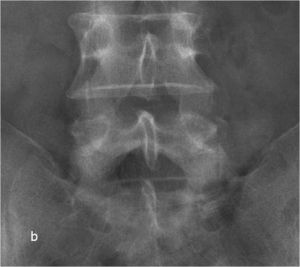

При рентгенографии (Рис.7) и МРТ (Рис.8) поясничного отдела позвоночника выявляется дегенеративный ретролистез L5 позвонка, секвестрированная парамедианная грыжа мп диска L5-S1 слева.

| Рис. 7а,b. Рентгенограмма поясничного отдела позвоночника в боковой (а) и прямой (b) проекциях до операции. Стрелкой показано смещение тела L5 позвонка кзади. | |